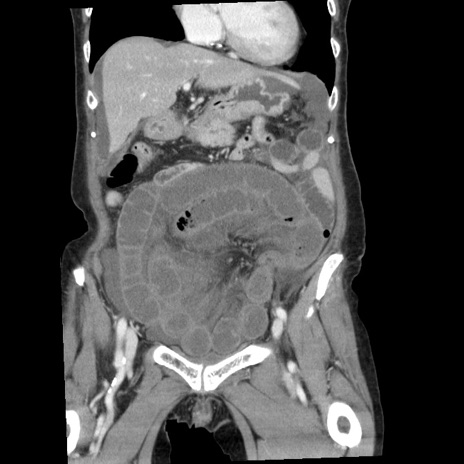

症例1(冠状断像)

【症例】80歳代女性

【主訴】腹痛

【現病歴】8時間前から腹痛あり来院。

【既往歴】糖尿病、脂質異常症、子宮体癌にて子宮全摘術

【身体所見】意識清明・会話良好だが腹痛で苦悶様、全腹部にわたって反跳痛と圧痛あり

【データ】WBC 13600、CRP 0.14、LDH 224、CK 90